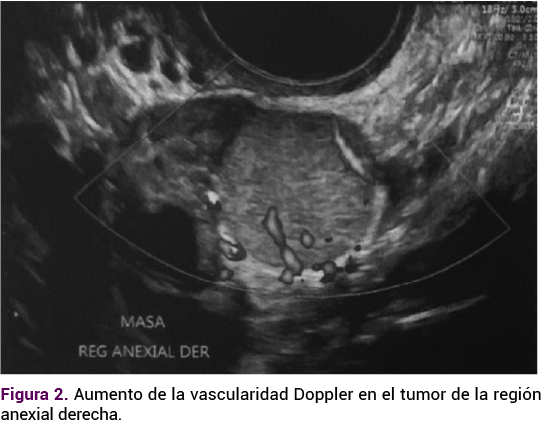

En el ultrasonido endovaginal el útero se encontró aumentado de tamaño debido a la miomatosis uterina intramural y subserosa de medianos elementos, con imagen isoecoica, extraovárica, de 26 x 20 x 18 mm, en la región anexial derecha entre el útero y el ovario ipsilateral, que a la aplicación de Doppler mostró aumento de la vascularidad.

Figura 2. Aumento de la vascularidad Doppler en el tumor de la región anexial derecha.